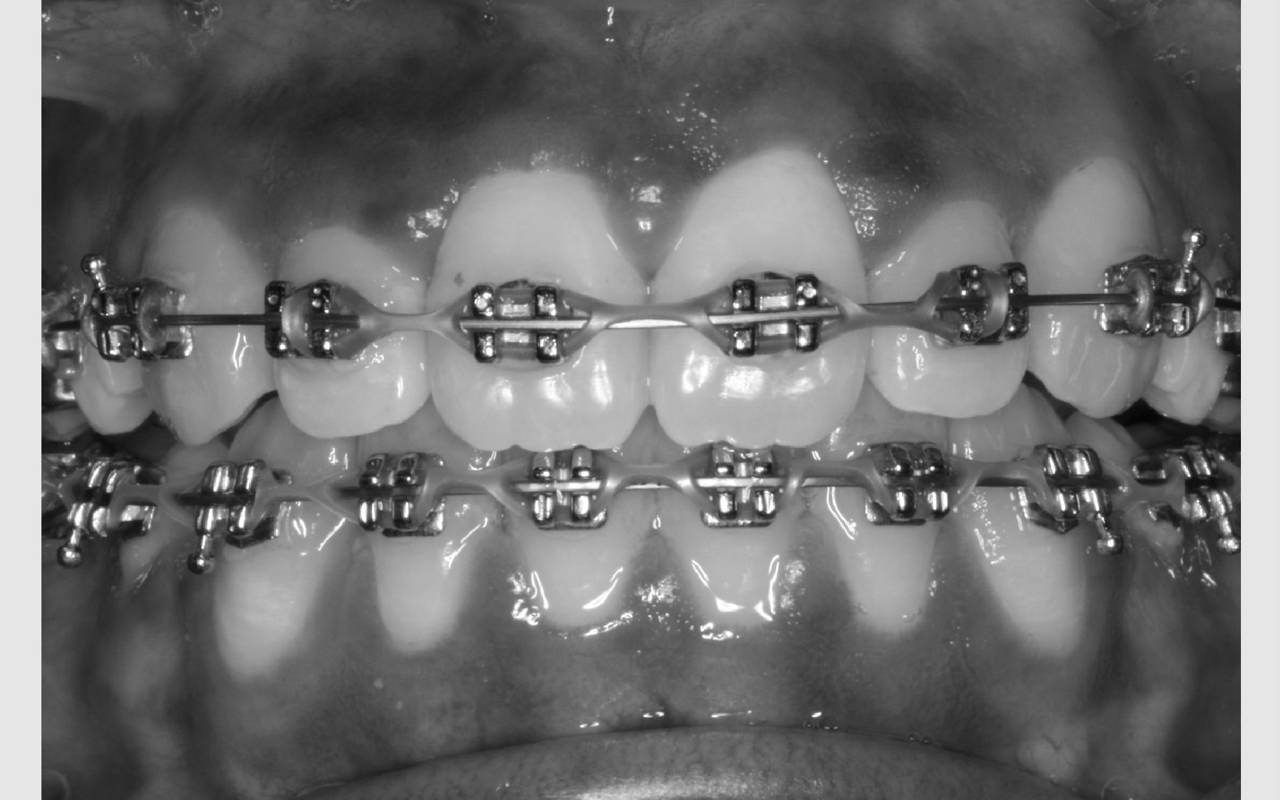

Hvor lang tid skal jeg have bøjle på?

Det tager i gennemsnit 2 år at få rettet tænder med fast bøjle, hvorefter du får nogle holdebøjler. Der limes ofte en tråd bag på fortænderne i over- og underkæbe. Derudover får du en skinne eller plade til at sove med hver nat i omkring to år efter, bøjlen er taget af. Disse holdebøjler er vigtige at bruge og holde ved lige, hvis man ønsker at bevare tænderne i deres nye position.

Så længe du er tilknyttet Aalborg Kommunes Tandpleje, varetager vi kontrollen af tænder og holdebøjler. Disse kontroller foregår på Tandreguleringsklinikken i mindst 2 år efter bøjlerne er taget af og herefter på den klinik, du er tilknyttet.

Efter du har forladt Aalborg Kommunes Tandpleje er det vigtigt, at din nye tandlæge overtager kontrollen. Dog er det allervigtigste, at du selv tænker over, at alt er som det skal være og reagerer, hvis det ikke er.

Det er vigtigt, at du selv sørger for at komme til kontrol, da tænderne kan flytte sig, hvis tråden går løs. Derudover kan der komme hul i tænderne, hvis det ikke opdages, at tråden løsnes.